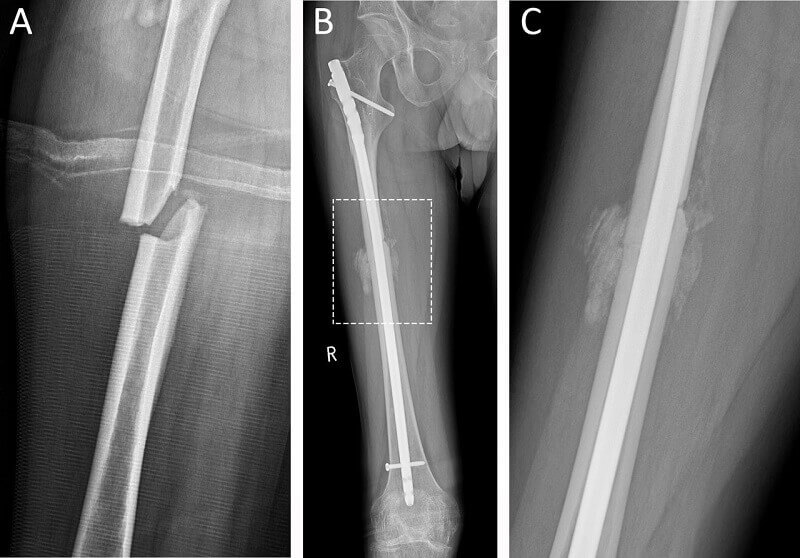

- قرار دادن نیل داخل عضلانی: عمل جراحی شامل درج میله فلزی (پلاتین ارتوپدی) در طول شافت استخوان ران است. پلاتین ران پا برای جوش خوردن استخوان ران شما استفاده میشود و به صورت دائم در بدن شما باقی میماند. به نقل از کتابخانه پزشکی آمریکا پلاتین درمان اولیه برای شکستگی استخوان ران نیست، مگر اینکه شکستگی افقی روی بخش پروگزیمال ران رخ دهد. معمولا مدت درمان شکستگی ران پا با پلاتین 2 ماه برای کودکان و برای بزرگسالان بین 3 تا 6 ماه است.